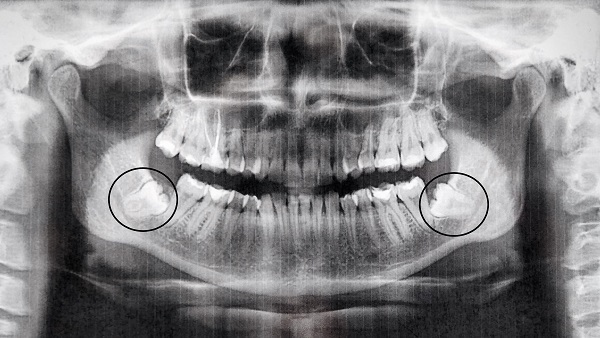

How does my dentist check my wisdom teeth?

Your dentist will look inside your mouth. If they cannot see your wisdom teeth because they are still under the gums, your dentist may ask to take an x-ray. This x-ray will let your dentist see your wisdom teeth. This helps your dentist to see the position of the teeth, the shape of the tooth's roots and if the wisdom teeth are close to important parts of your face, such as nerves. If you are having your wisdom teeth removed, the x-ray helps your dentist plan this treatment.